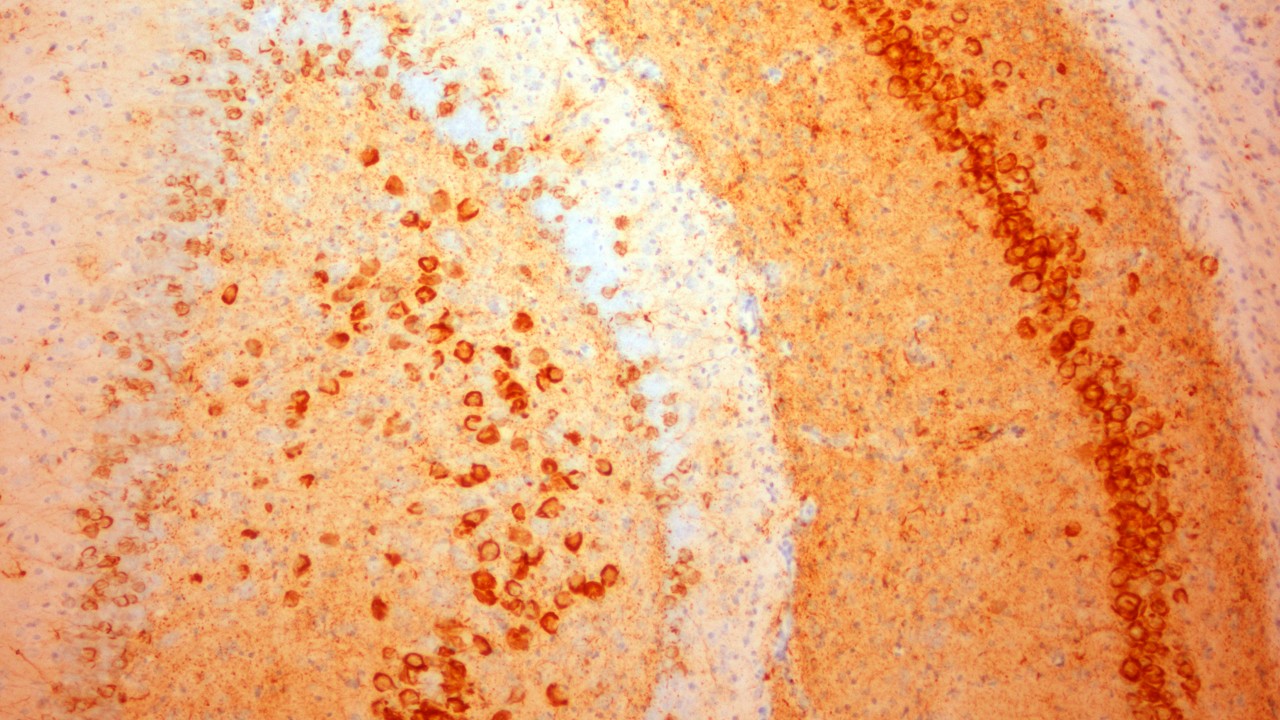

脳は人体の中で最も複雑かつ最も重要な臓器です。1,000億個とも言われるニューロンからなり、中枢神経系の一部として五感から全身の筋肉まで人体のすべてを制御しています。